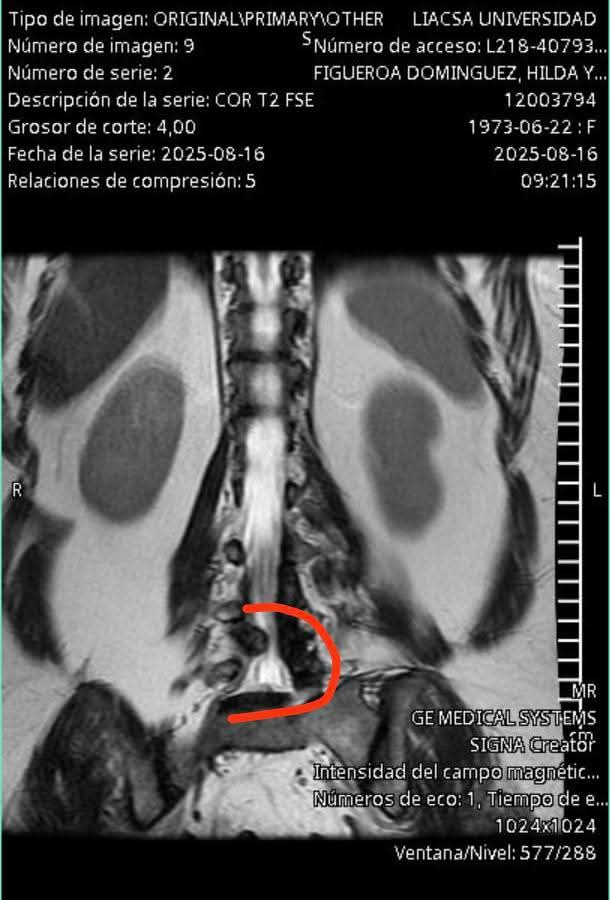

H. Cd de Chihuahua. – En la colonia Deportistas, de la ciudad de Tecomán, Hilda Yolanda Figueroa Domínguez vive días de angustia y esperanza. Desde febrero espera una cirugía en el Seguro Social para atender dos hernias en la columna y un quiste que, según los médicos, sigue creciendo y le está quitando movilidad.